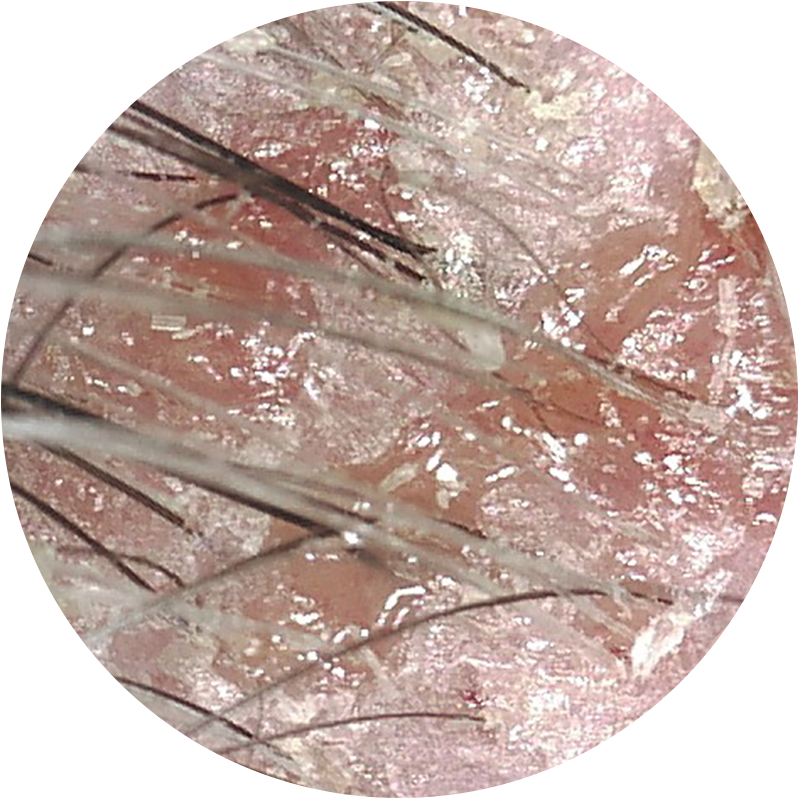

Visión Cámara Tricoscópica

ANTES

Alopecia androgenética

3 meses de tratamiento